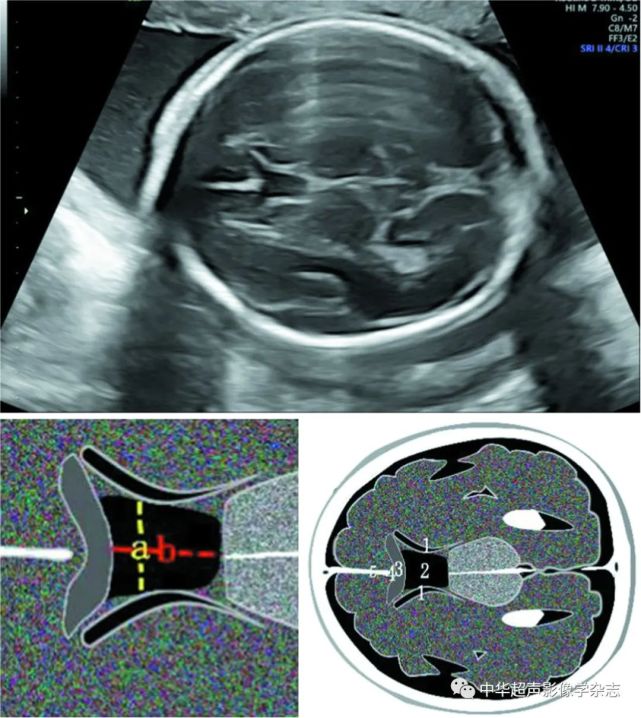

产前超声可在胎儿头颅3个标准切面:经丘脑水平横切面,经侧脑室水平横

图2当出现脑室扩张时,胎儿需要接受详细的超声检查或进一步行头颅磁

图2产前超声声像图及模式图示侧脑室后角扩张呈"泪滴征*示,透明隔